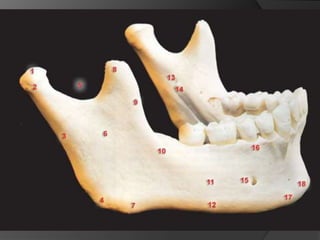

EVALUACIÓN DE PILARESProporción corona-raizConfiguración de la raízZona del Ligamento Periodontal (Ley de Ante)

Tylman: afirmó que dos dientes pilares son capaces de soportar dos póntIcos.Johnston y col.: LEY DE ANTELa superficie radicular de los dientes pilares, con soporte óseo periodontal, debe ser mayor o igual a la de los dientes a sustituir con pónticos